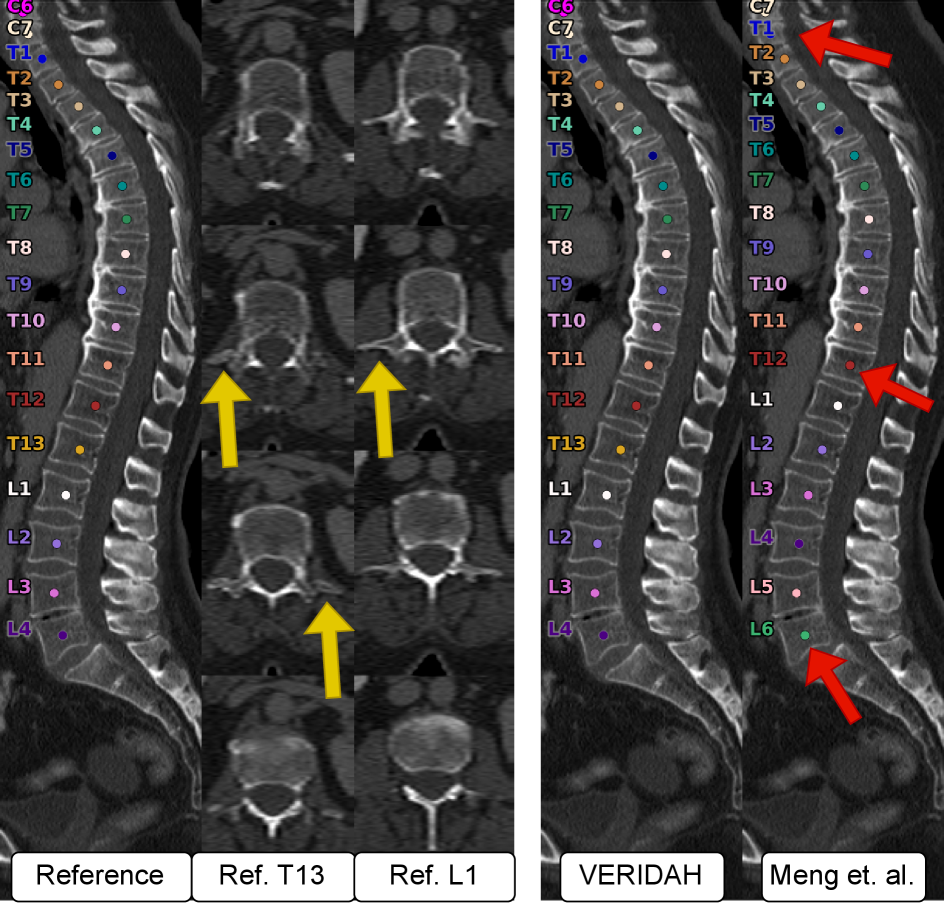

4.1 CT

VERIDAH achieves significantly better metric values than Meng et al. (see Table 3, all ). While Meng et al. provide decent results for LEA recall, they fail to correctly annotate TEA cases, regardless of whether we set their anomaly penalty cost to zero. Notably, VERIDAH achieves better performance on non-anomalous cases, as indicated by the superior subject correctness with much higher mean and lower standard deviation. When we set the punishment cost for TEA to zero, their perfect label percentage drops slightly while the TEA recall significantly increases. However, with compared to VERIDAH’s , this is still inferior. For a qualitative example, see Figure 4. Notably, on our test set, in contrast to Meng et al., the predicted labels of VERIDAH were never shifted by more than one (see Figure 5 for example).